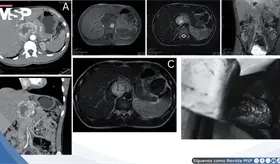

Lo que comenzó como un cuadro frecuente de dolor pélvico y dismenorrea en una mujer, terminó siendo un carcinoma folicular originado en estruma ovárico maligno. La paciente tenía solo 35 años, marcadores tumorales completamente normales y ninguna alteración tiroidea.

El estudio histológico confirmó un adenocarcinoma mucinoso de células en anillo de sello de vejiga con invasión muscular y diseminación metastásica pulmonar y ósea.